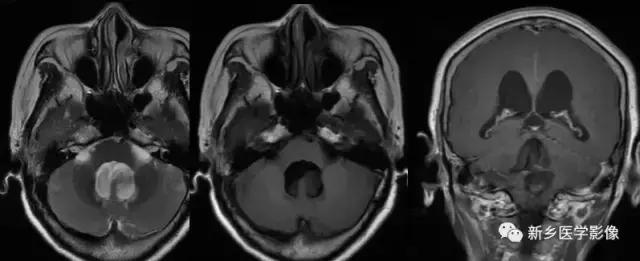

4.Dandy-Walker’s综合症

又称第四脑室中侧孔先天性闭锁。在胚胎早期期,第四脑室正中孔及侧孔闭寒,导致四脑室呈囊性扩张,并伴有小脑蚓部及半球发育不良,扩张之四脑室向后发展,并与枕大池相连,使后颅窝扩大,小脑幕抬高。本病出现脑积水通常见于婴儿期,或者出生后即存在,但到成人期才发病。

2.小脑扁桃体下疝畸形

又称Chiari’s畸形,即小脑扁桃体下移到椎管内,延髓、四脑室延长并部分向下移位。可分为3型。各型均常有脑积水表现。三脑室及侧脑室扩大。Ⅰ型:若仅有小脑扁桃体下移。扁桃体下缘低于枕大孔连线5mm以上,无脑干及四脑室改变者为Ⅰ型。Ⅱ型:除小脑扁桃体下移外,同时有四脑室部分或全部降入枕大孔以下者为Ⅱ型。Ⅲ型:全小脑及四脑疝入枕大孔以下者为Ⅲ型。